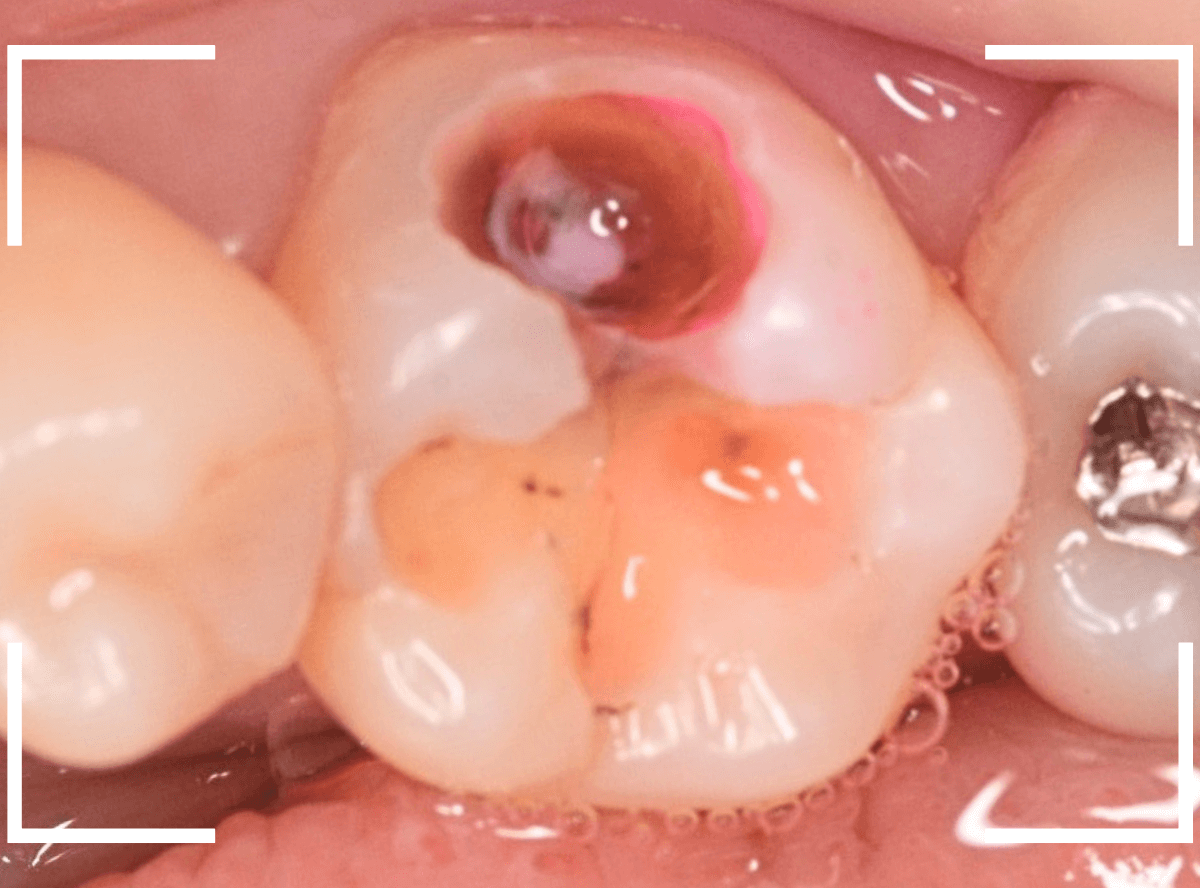

レジンを外すと、中から出血してきました。

これは、歯のスキマに歯肉が入り込んでしまったために起こってしまったものです。

おそらく、随分前から虫歯が進行していたと思われます。

止血しながら、電気メスで歯の中に入り込んだ歯肉を除去します。

虫歯と入り込んだ歯肉でぐちゃぐちゃになっている状態でした。

これでは、痛みが出てもおかしくありません。

慎重に全ての虫歯を除去したところです。

〇部が神経の入り口が見えているところです。